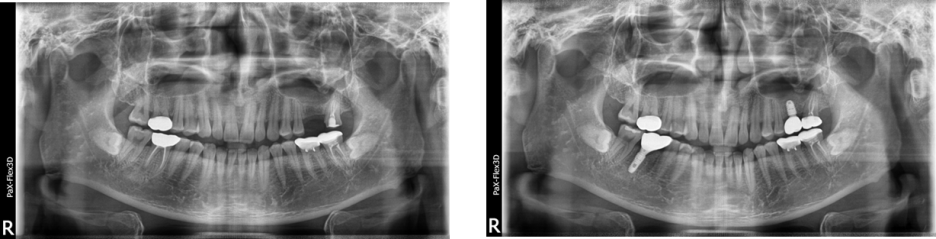

39세 남성

(전) 2021-12-07 (후) 2022-08-29

상악 잇몸뼈 부족으로

상악동거상술 후 임플란트 진행한 사례